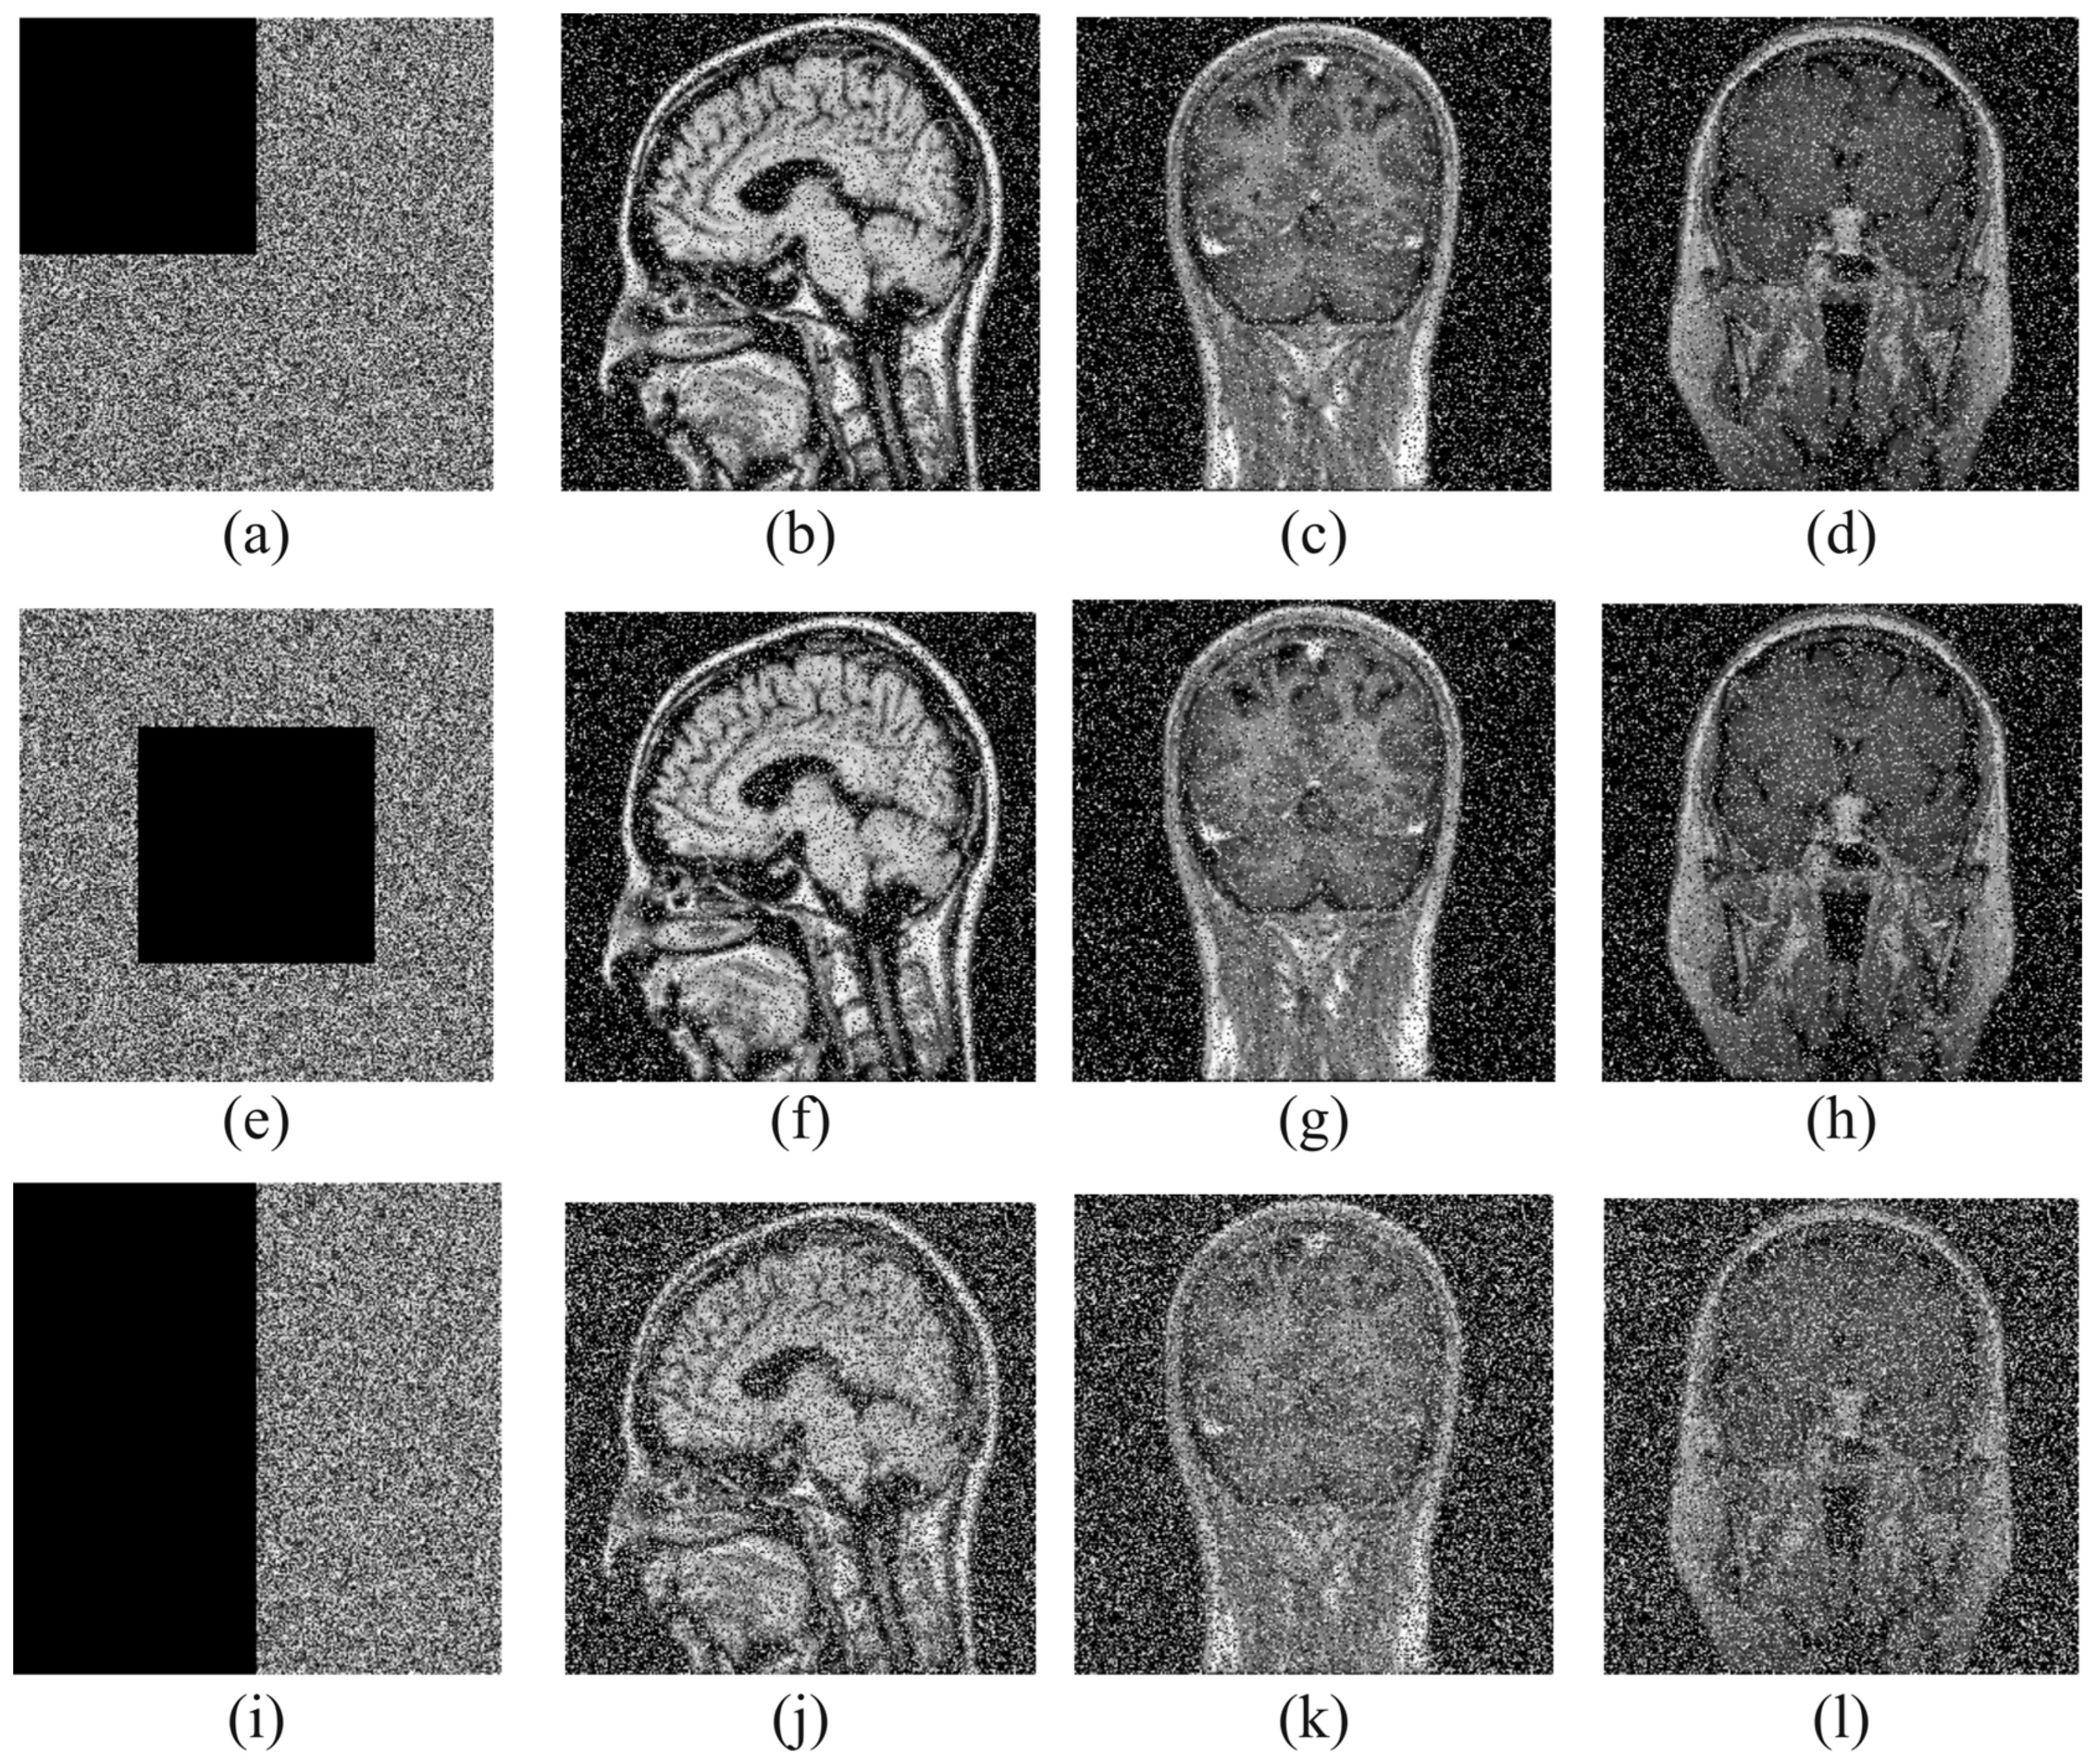

Occlusion occurs when the encrypted data are partially or completely lost. In order to evaluate how effective the encryption method used is against occlusion, the encrypted images are cut at ¼ (corner), ¼ (middle), and 1/2 and reconstructed. Figure 7 shows the test results for data loss attacks.

Figure 7.

Decryption results with ¼(corner), ¼(middle), and 1/2 occlusion ratios, respectively: (a) ¼(corner) occlusion and its decryption images (b–d); (e) ¼(middle) occlusion and its decryption images (f–h); (i) 1/2 occlusion and its decryption images (j–l).

Distortion is usually evaluated using the peak signal-to-noise ratio (PSNR), defined in Equation (13), which measures the ratio between the signal’s highest potential power and the distortion that occurs. The higher the PSNR, the better the image quality.

Here, MSE is the mean square error and is calculated as follows:

where eij is the source image, and fij is the decrypted image. Table 8 shows the PSNR values obtained as a result of occlusion.

Table 8.

PSNR value of images obtained as a result of occlusion.

Although there are some distortions on the reacquired images, the main information of the images can still be recognized. Therefore, the proposed method is proved to be robust against data loss attacks.